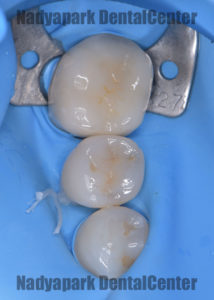

レントゲン写真撮影の結果、右下の奥歯の虫歯が進行していることが分かったので虫歯を除去し、型取りをしてからラバーダム装着下でセラミックの詰め物を装着しました。

ラバーダムの使用には以下のような利点があります。

・歯やセラミックに唾液、血液などの水分の付着を防ぐ

・歯とセラミックの接着力低下の防止

・薬液がお口の中に入らない

・器具や材料の飲み込みを防止

・舌や頬を傷つけない